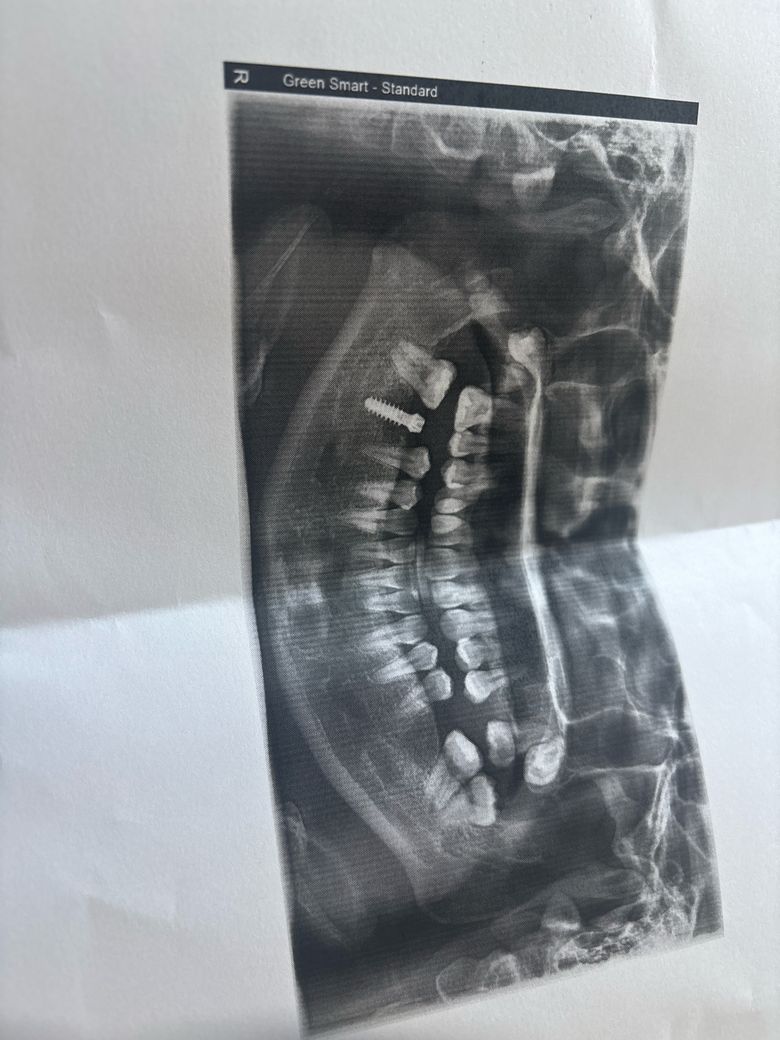

상악매복사랑니 빼기 쉬운편인가요 ? 다음주 월요일 상악동 거상술 동시예정입니다

다음주 월 상악동 거상술 예정입니다 무통 마취 후 하면 괜찮겠죠 ? 다른 치과에서 이빨 발치 할때 오랜 시간과 소리 냄새 물 튀는것 때문에 공포심이 극도로 많이 생겼습니다 숨이 가쁘고 안쉬어질 정도에요 그래도 디지털 임플란트라 하나하나 하고 있는중인데 ....측방거상술과 치조정 예정중인데 측방 거상술 후기를 찾아보니 너무 무서워서요 ...수면마취를 요구했는데 회복하는데 오랜시간 걸리고 부분마취로 충분히 할수있다고 안해준다 하더라구요 ....매복 사랑니도 빼기 쉬운편인가요 ? Ibs 매직코어로 임플란트를 하는데 선생님께서 30-40분안에 즉시식립하고 빨리 끝난다 하시는데 맞나요 ?

매복된 사랑니는 매우 깊게 매복되어 있어서 발치를 하는데 어려움이 있을것으로 생각됩니다. 수면마취를 하게 되면 통증이나 불안감이 상대적으로 줄어들게 됩니다.

위쪽 치아는 시야 확보만 잘되면 발치는 크게 어렵지 않습니다. 수술을 잘하신다면 금방 끝날것같습니다.

임플란트를 하면서 같이 진행하는 경우에는 사랑니를 발치하는 것 또한 난이도가 어렵진 않습니다.

쉬운 난이도의 매복 사랑니는 아니지만 구강외과 전문의의 숙련도에 따라 다를 것 같습니다. 치과 공포증이 큰 경우 당연히 수면마취 요청할 수 있습니다. 비용만 추가로 들뿐입니다.